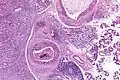

Their histologic appearance is similar to ductal breast carcinoma.

Intermed. mag. -